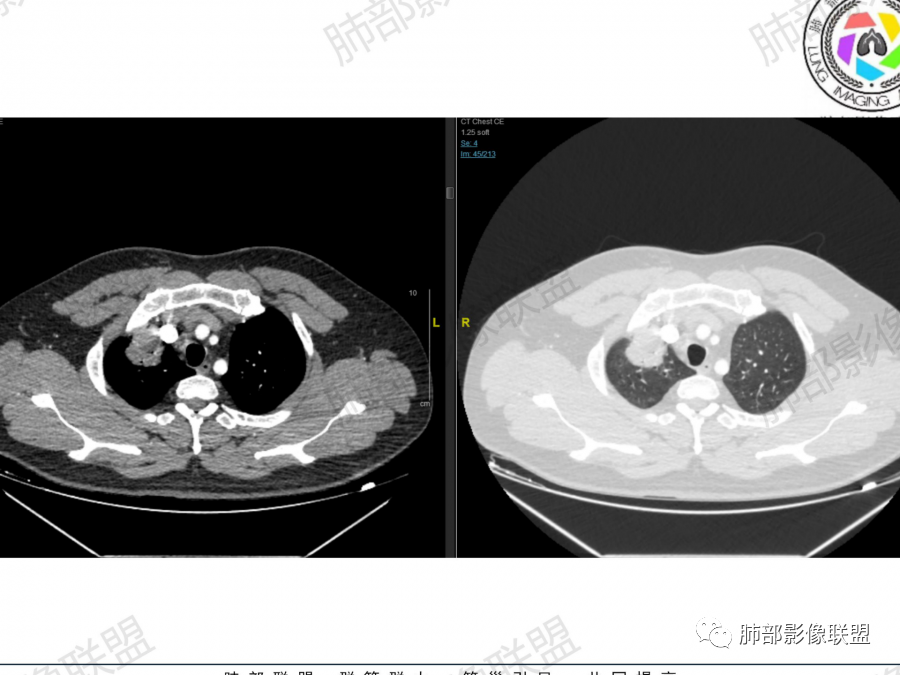

主要征象:右肺多发病变  一元论?二元论?

1.右上肺团块:分叶,不均性强化,其内支气管走行自然,增强血管影可见、清晰。

疑问:空洞还是残余肺组织?

2.右下肺结节、实变:胸膜下,长轴平行胸膜。部分似有晕影。支气管进入后近段截断